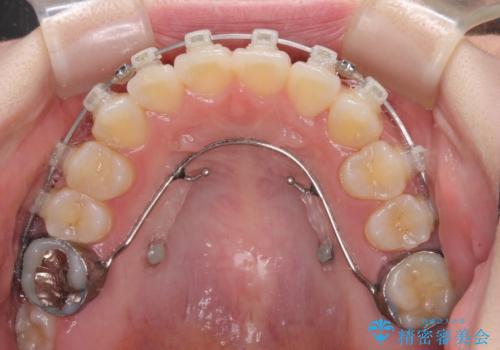

- クリアブラケット

挺出した大臼歯を元の位置に戻すことは現実的に難しいため抜歯することとし、補助装置とワイヤー装置により上顎歯列全体を後方に移動することとしました。

順調に後方移動することができ、わずか1年強で治療を終えることができました。